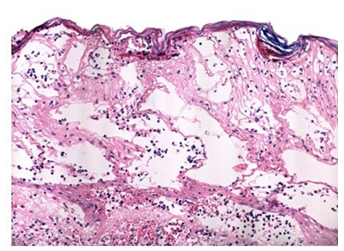

Una semana después se sospechó herpes simple resistente a acyclovir en paciente inmunosuprimida y se solicitaron exámenes paraclínicos para inicio de foscarnet y se tomó biopsia de piel, la cual mostró múltiples neutrófilos invadiendo la dermis y la epidermis sin vasculitis (figuras 1 y 2).

La histología es inespecífica y su principal papel es descartar otros diagnósticos diferenciales como infección, vasculitis, malignidad, etc. En la biopsia de piel se observa infiltrado neutrofílico. La forma vegetativa puede mostrar granulomas con formación de tractos fistulosos y la ampollosa se caracteriza por presentar ampollas subepidérmicas. Siempre se deben enviar muestras para cultivos 1,6,15).